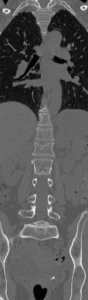

Tomografia Computada

TC ventanas de partes blandas y óseas. MPR en planos coronal y sagital. Permite caracterizar mejor la fractura, confirmar la protrusión del muro posterior hacia el canal. Descartar hematomas epidural y paravertebral.

Qué agrega la TC (y qué reportar):

- Define la morfología de la fractura (compresión vs estallido) y el grado de conminución.

- Evalúa el muro posterior y la posible retropulsión hacia el canal.

- Valora compromiso de arcos posteriores (pedículos, láminas, apófisis espinosas/transversas).

- Permite medir de forma más confiable la pérdida de altura y la angulación.